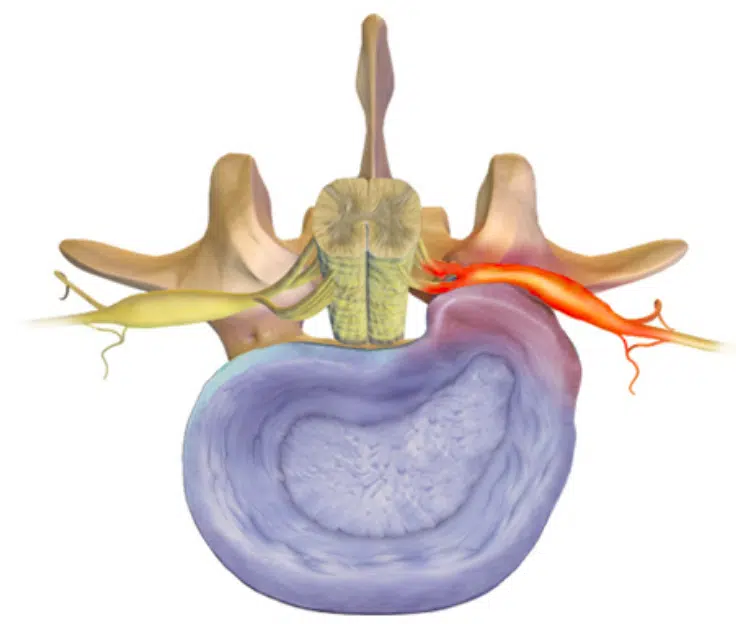

Har lokalisasjon noe å si for utfallet?

Vi vet at de fleste prolapser skjer subartikulært (3 av 4). I følge SPORT-studien er det dårligere prognose ved alle typer prolapser annet en subartikulært (18). Da tror jeg ikke man snakker om de sentrale prolapser, da disse sjeldnere gir plager (så lenge det ikke er en kjempestor prolaps som gir cauda equina syndrom). Man snakker da om de foraminale og ekstraforaminale prolapser. Pasientene med foraminal og ekstraforaminal prolaps kan ha et sterkere symptombilde, da skivemateriale kan trenge ut i en trangere kanal med begrenset plass til forskyvning av nerven. Spinalganglion til bakre horn befinner seg også her, som også er en potensielt smertesensitiv struktur (30,31). Det er også andre studier som viser at disse pasientene har noe dårligere resultater av både operasjon og konservativ behandling (32,33).